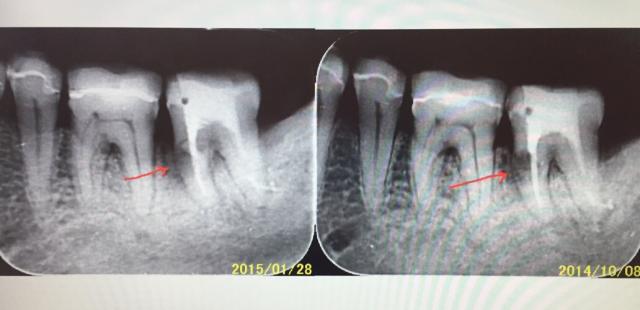

珍しい歯の内部吸収症例

歯の内部(歯髄)部分から吸収が起こり、最終的には歯が折れてしまう珍しい内部吸収について

頻度としては私の全患者のうち年間で1人いるかいないかというとても珍しい現象である。大抵のケースでは気づかないうちに徐々に進行して歯髄炎のような症状から発見されることが多いのが特徴である。強い咬合力がかかっている歯にストレスがかかると時として歯の内部吸収がおこるようである。

以前はメインテナンス時にはパノラマレントゲンで歯の虫歯や歯周病を確認していたのだが、2年前から14枚法のデンタル撮影のIPフィルムにに切り替えてからは発見が容易になっている。

今回のケースでは抜髄処置後に管内の内部吸収部にはMTAセメントを使用して歯の外部との交通部分を埋めて内部はファイバーコア+スーパーボンドで補強をして歯を抜かずに保存していく予定である。

左上の画像はわずか2年で内部吸収がおこった例

左下は内部吸収後にフラップ手術で管外からMTAセメント+CRで処置した例